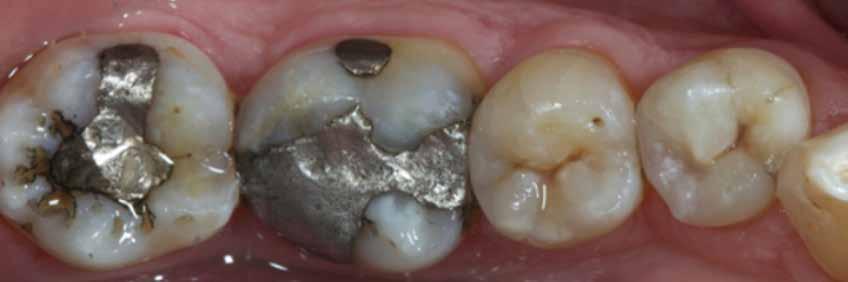

2. ábra: A páciens egy nem megfelelő I. osztályú ezüst-amalgám töméssel és II. osztályú szuvasodással jelentkezett. A fog izolálása kofferdám alkalmazásával történt.

3. ábra: A preparálás, a bondozás és a kompozit felvitele után. (Megjegyzés: némi kompozit túlfolyás látható a mesiális doboz axiális falain).

4. ábra: A durva finírozás után a restauráció pereme sima és anatómiailag is megfelelő.

Klinikai példa az 2–4. képeken látható.